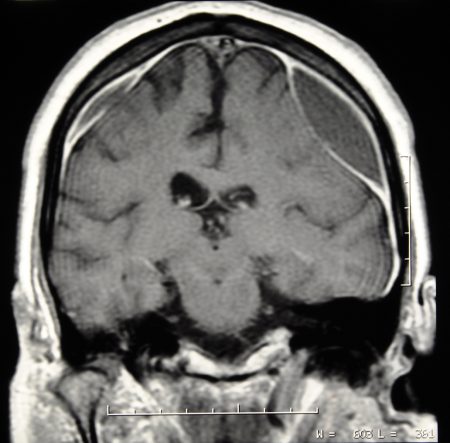

Brain CT scan with subdural hematoma